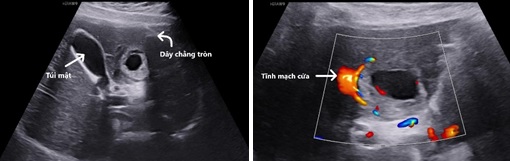

Hình ảnh siêu âm:

Hình 1, 2: Túi thai nằm ở hạ phân thùy IVb gan trái, giữa dây chằng tròn và túi mật. Tăng sinh mạch máu quanh túi thai, túi thai nằm rất sát một nhánh của tĩnh mạch cửa trái.